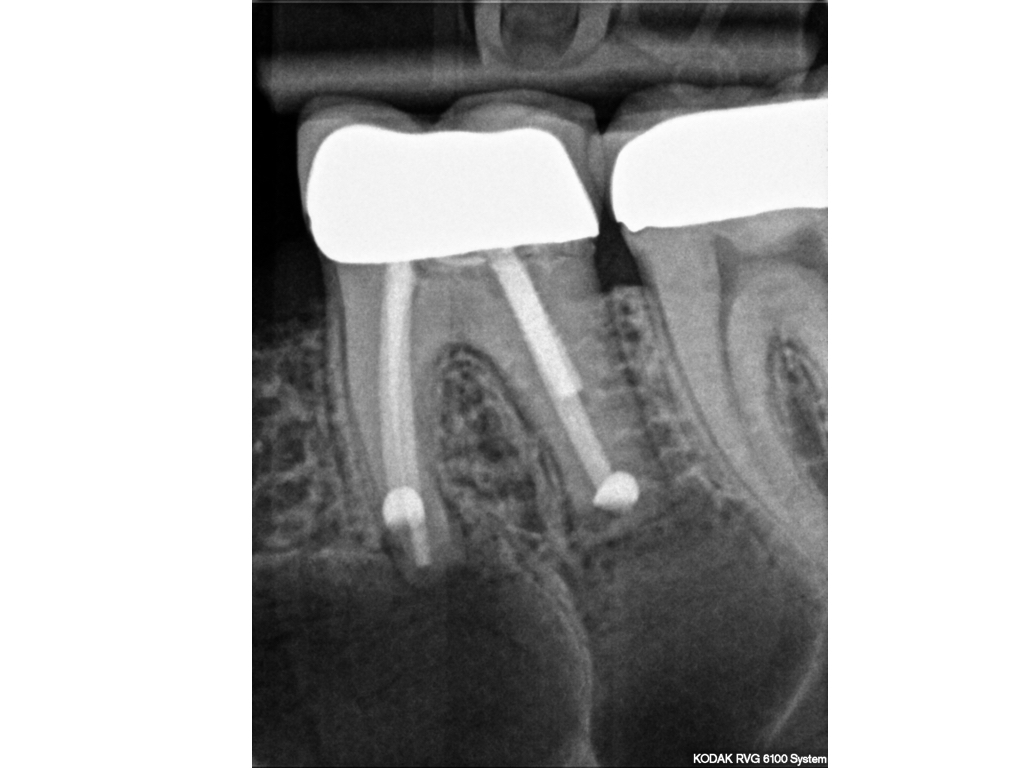

WS_141.002

Eine Fallvorstellung